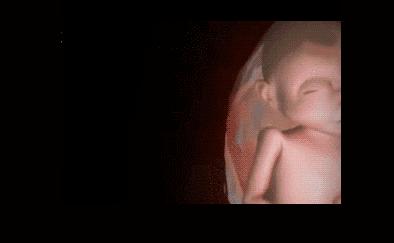

其实小家伙很小的时候就已经开始“闹腾”了:妥妥的一个运动健将!

小碎步向前缩,撅着小屁股用力一蹬,身体向后滑去——“母胎版蛙泳”动作很标准嘛!

等到他再大点的时候,“蛙泳”项目已经无法进行了,但是你以为他长大点了就会听话、懂事,当个乖宝宝吗?